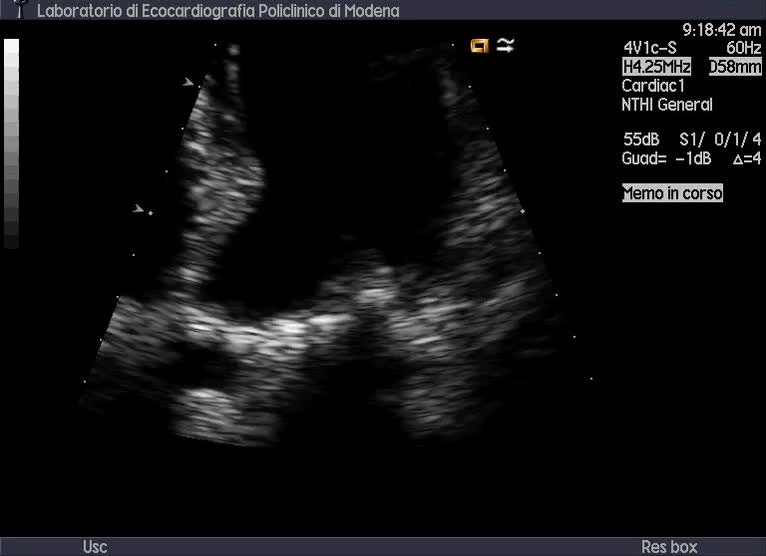

Titolo:

Vegetazioni sul setto interventricolare membranoso e ascesso

Autore:

Andrea Barbieri